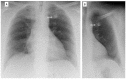

Objectives: To evaluate the capability of digital tomosynthesis (DTS) to characterize suspected pulmonary lesions in the so-called hidden areas at chest X-ray (CXR).

Materials and methods: Among 726 patients with suspected pulmonary lesions at CXR who underwent DTS, 353 patients (201 males, 152 females; age 71.5 ± 10.4 years) revealed suspected pulmonary lesions in the apical, hilar, retrocardiac, or paradiaphragmatic lung zones and were retrospectively included. Two readers analyzed CXR and DTS images and provided a confidence score: 1 or 2 = definitely or probably benign pulmonary or extra-pulmonary lesion, or pulmonary pseudo-lesion deserving no further diagnostic work-up; 3 = indeterminate lesion; 4 or 5 = probably or definitely pulmonary lesion deserving further diagnostic work-up by CT. The nature of DTS findings was proven by CT (n = 108) or CXR during follow-up (n = 245).

Results: In 62/353 patients the suspected lung lesions were located in the lung apex, in 92/353 in the hilar region, in 59/353 in the retrocardiac region, and in 140/353 in the paradiaphragmatic region. DTS correctly characterized the CXR findings as benign pulmonary or extrapulmonary lesion (score 1 or 2) in 43/62 patients (69%) in the lung apex region, in 56/92 (61%) in the pulmonary hilar region, in 40/59 (67%) in the retrocardiac region, and in 106/140 (76%) in the paradiaphragmatic region, while correctly recommending CT in the remaining cases due to the presence of true solid pulmonary lesion, with the exception of 22 false negative findings (60 false positive findings). DTS showed a significantly (p < 0.05) increased sensitivity, specificity, and overall diagnostic accuracy and area under ROC curve compared to CXR alone.

Conclusions: DTS allowed confirmation or exclusion of the presence of true pulmonary lesions in the hidden areas of the chest.